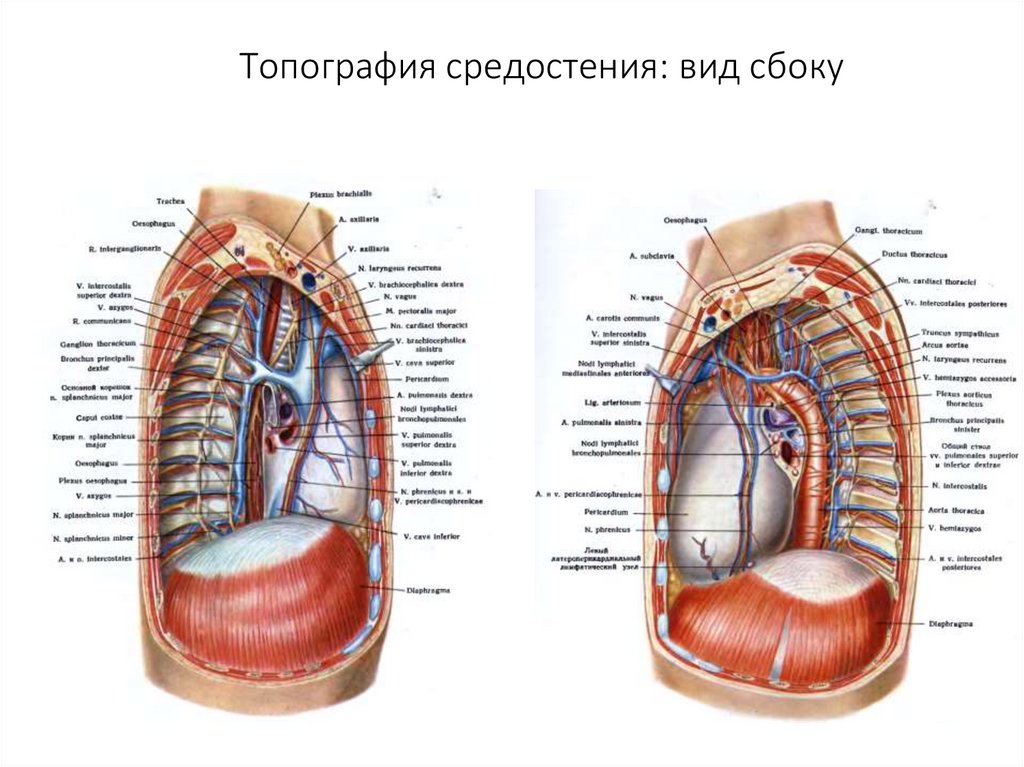

Анатомия Сердца: Расположение и Функции